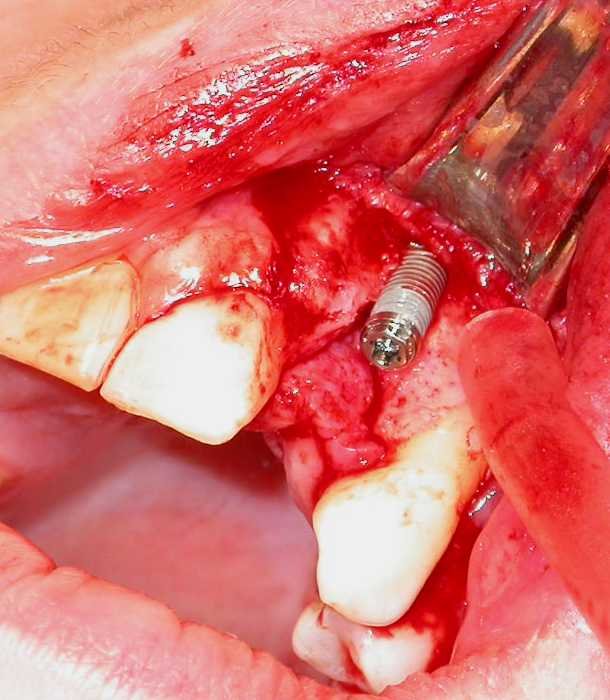

Individual implant placement

This is usually performed under local anaesthesia [treatment-surgery-anaesthesia-preamble] with or without sedation. The residual alveolar ridge is exposed by a crestal incision and mucoperiosteal flaps are raised medially and laterally. The bone is prepared by drilling at slow speed with meticulous irrigation to avoid osteocyte death caused by bone overheating. The implant site is prepared by sequentially increasing twist drill size to reach one just under the maximum diameter of the implant. Depending on bone density and implant design, the bone is tapped (prepared for a thread) before placing the implant. This is also done under coolant irrigation (Figure 7).

Figure 7: Implant socket preparation.